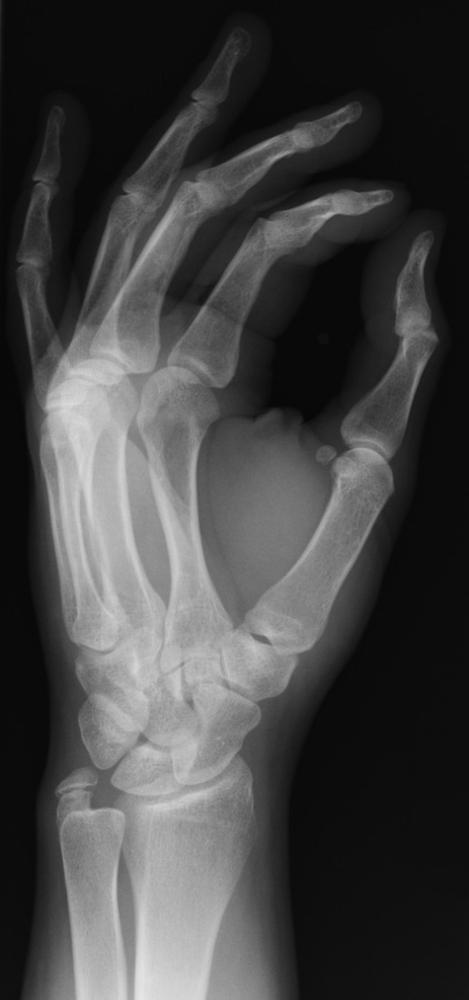

Съпругата му Анна Берта е първият човек, сдобил се с рентгенова снимка. Тя била на ръката й. Когато видяла снимката на скелетната кост, ужасената съпруга възкликнала: „Господи! Видях смъртта си!“